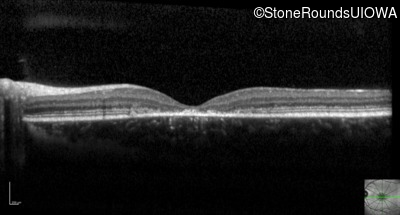

Optical Coherence Tomography - Right -

20/100 -2

Optical Coherence Tomography - Left -

20/100

Visit at age: 11 years

AR Stargardt Disease (IIA)

AR Stargardt Disease

ABCA4

Gly1961Glu GGA>GAA, Arg212Cys CGC>TGC